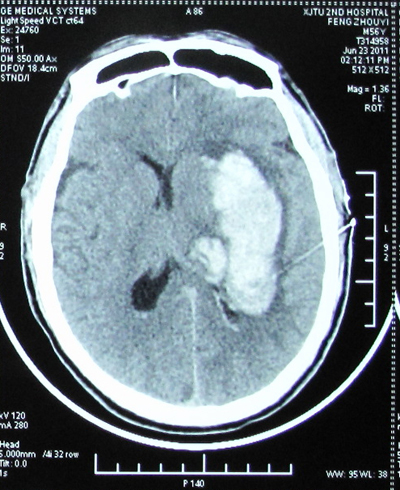

患者男性,56岁,因“突发左侧肢体活动不灵19小时,意识不清18小时” 于2011年6月23日急诊收住我科,复查颅脑CT显示“右侧基底节区及丘脑出血(量约68毫升)并破入脑室”。完善各项术前准备后,在手术麻醉科张珍妮主治医师、薛鹏军以及我科宋琴的协助下,吕健副主任医师主刀、宋千、权瑜担任助手,在全麻下为患者施行了完全神经内镜下右侧基底节区血肿清除术,手术顺利,未输血,术后患者清醒,正在康复中。